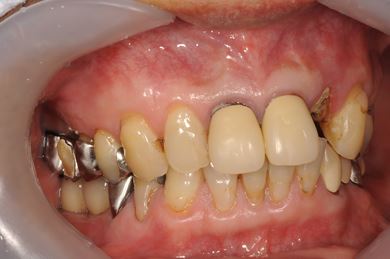

インプラントの症例写真 IMPLANT

| 性別/年齢 | 男性 / 61歳 | ||||||||||||||||||||||||||||||||

| 主訴 | 奥歯のインプラント治療を希望。 | ||||||||||||||||||||||||||||||||

| 治療内容 | インプラント4本、メタルボンドセラミッククラウン4本 | ||||||||||||||||||||||||||||||||

| 総治療費 | 1,508,220円 | ||||||||||||||||||||||||||||||||

| 治療期間 | 7ヶ月 |